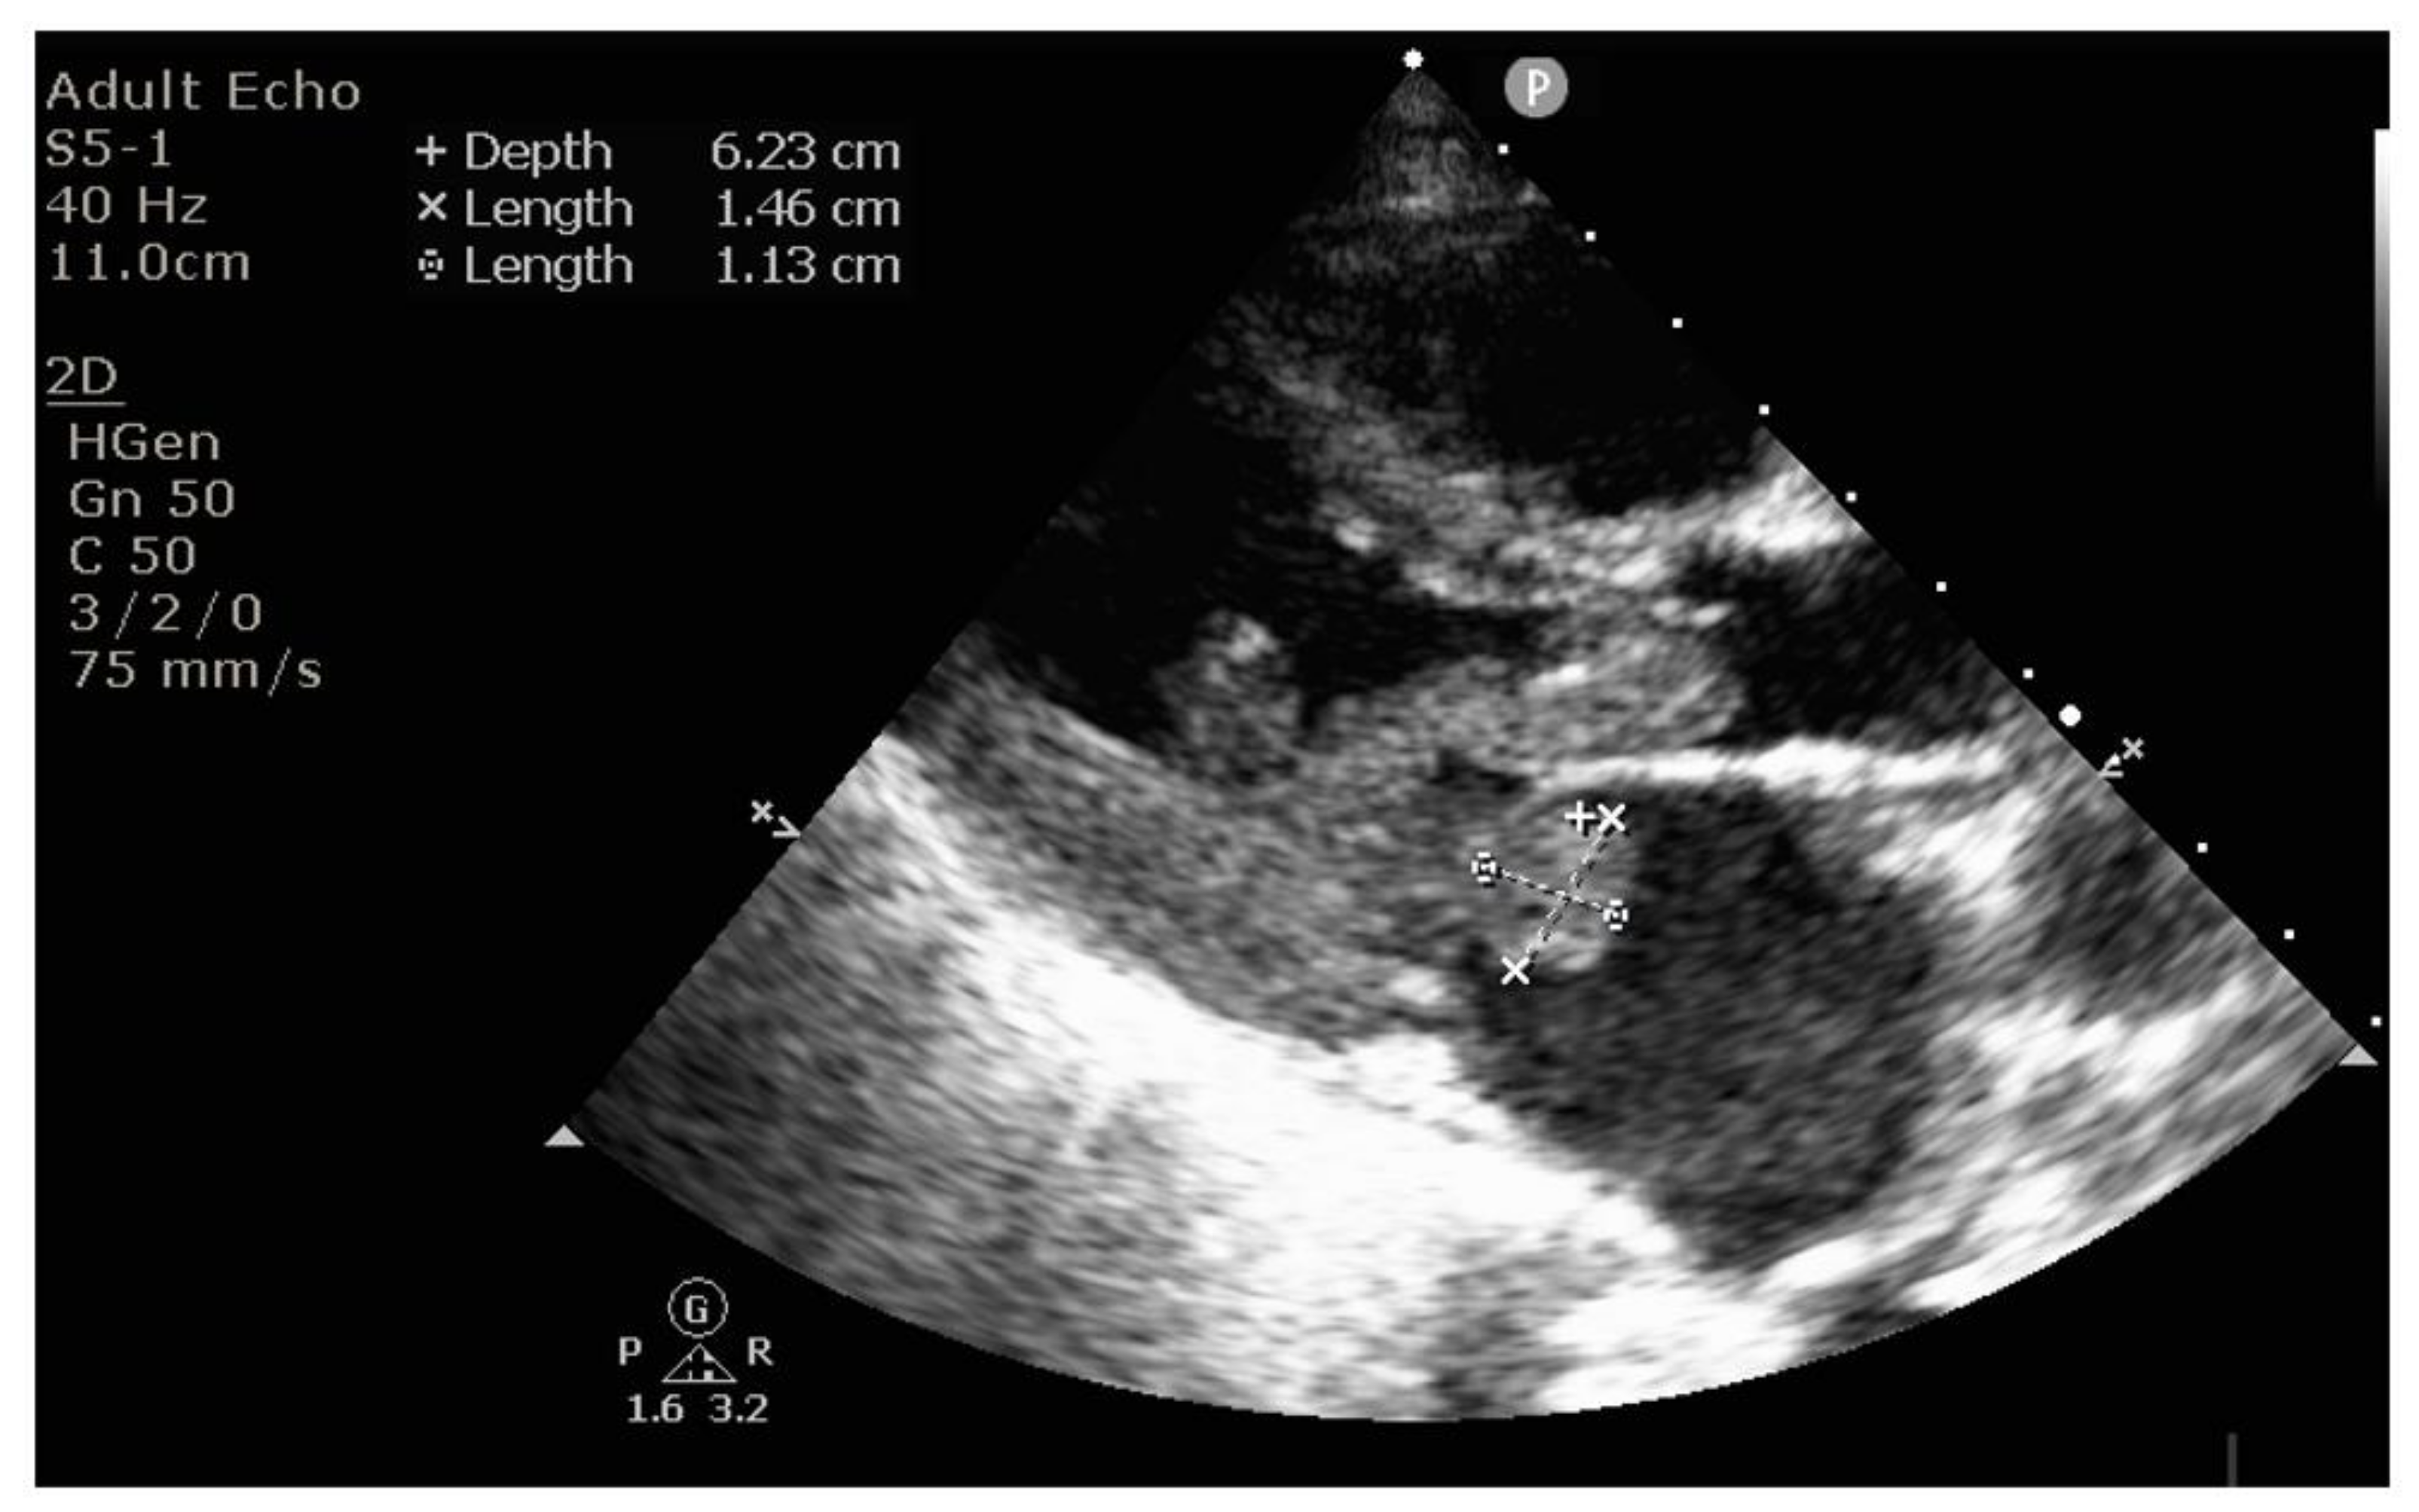

2. Case Report